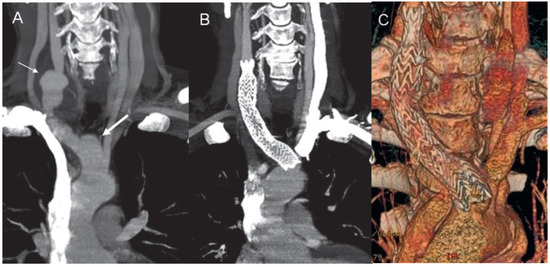

Figure 2.

Abdominal aortic wall thickening (A) with involvement of the iliac arteries (B) and epiaortic branches (C). CT angiography showing the aneurysm of the right common carotid artery with thickening of the wall and suspected thrombus (D).

A 52-year-old male was admitted to our hospital with a fever of unknown origin and raised inflammatory parameters (CRP 251 mg/l, ESR 50 mm/h) in March 2006. He had a history of recurrent pyoderma gangrenosum (PG) of the lower extremities since the age of 14 years old. After numerous attempts with various immunosuppressive agents, stable remission was finally achieved using local tacrolimus applications (Figure 1). Physical examination except for scarring after PG lesions in the lower limbs was otherwise unremarkable. To search for the possible causes of inflammatory syndrome thoraco-abdominal computed tomography (CT) was performed. It revealed thoracic and abdominal aortic wall thickening (Figure 2, panel A) with involvement of epiaortic branches (Figure 2, panel C), the coeliac trunk, the superior mesenteric artery and iliac arteries (Figure 2, panel B). 18FDG positron emission tomography (PET) revealed the presence of active inflammatory aortic wall processes at the level of the thoracic and abdominal aorta as well as the aortic arch branches, the left coronary artery and the iliac arteries. The duplex scan of the temporal arteries was negative for the signs of giant cell arteritis (GCA), and the patient did not present any typical clinical signs of this vasculitis (e.g., localised headache, visual disturbance, tenderness of the temporal artery or jaw muscle pain). Therefore, radiological findings of large vessel vasculitis without evidence of other inflammatory disorders (ANCA, ANA, HLA B5, HLA B25 negative) in association with PG made the diagnosis of Takayasu arteritis (TA) the most likely one.